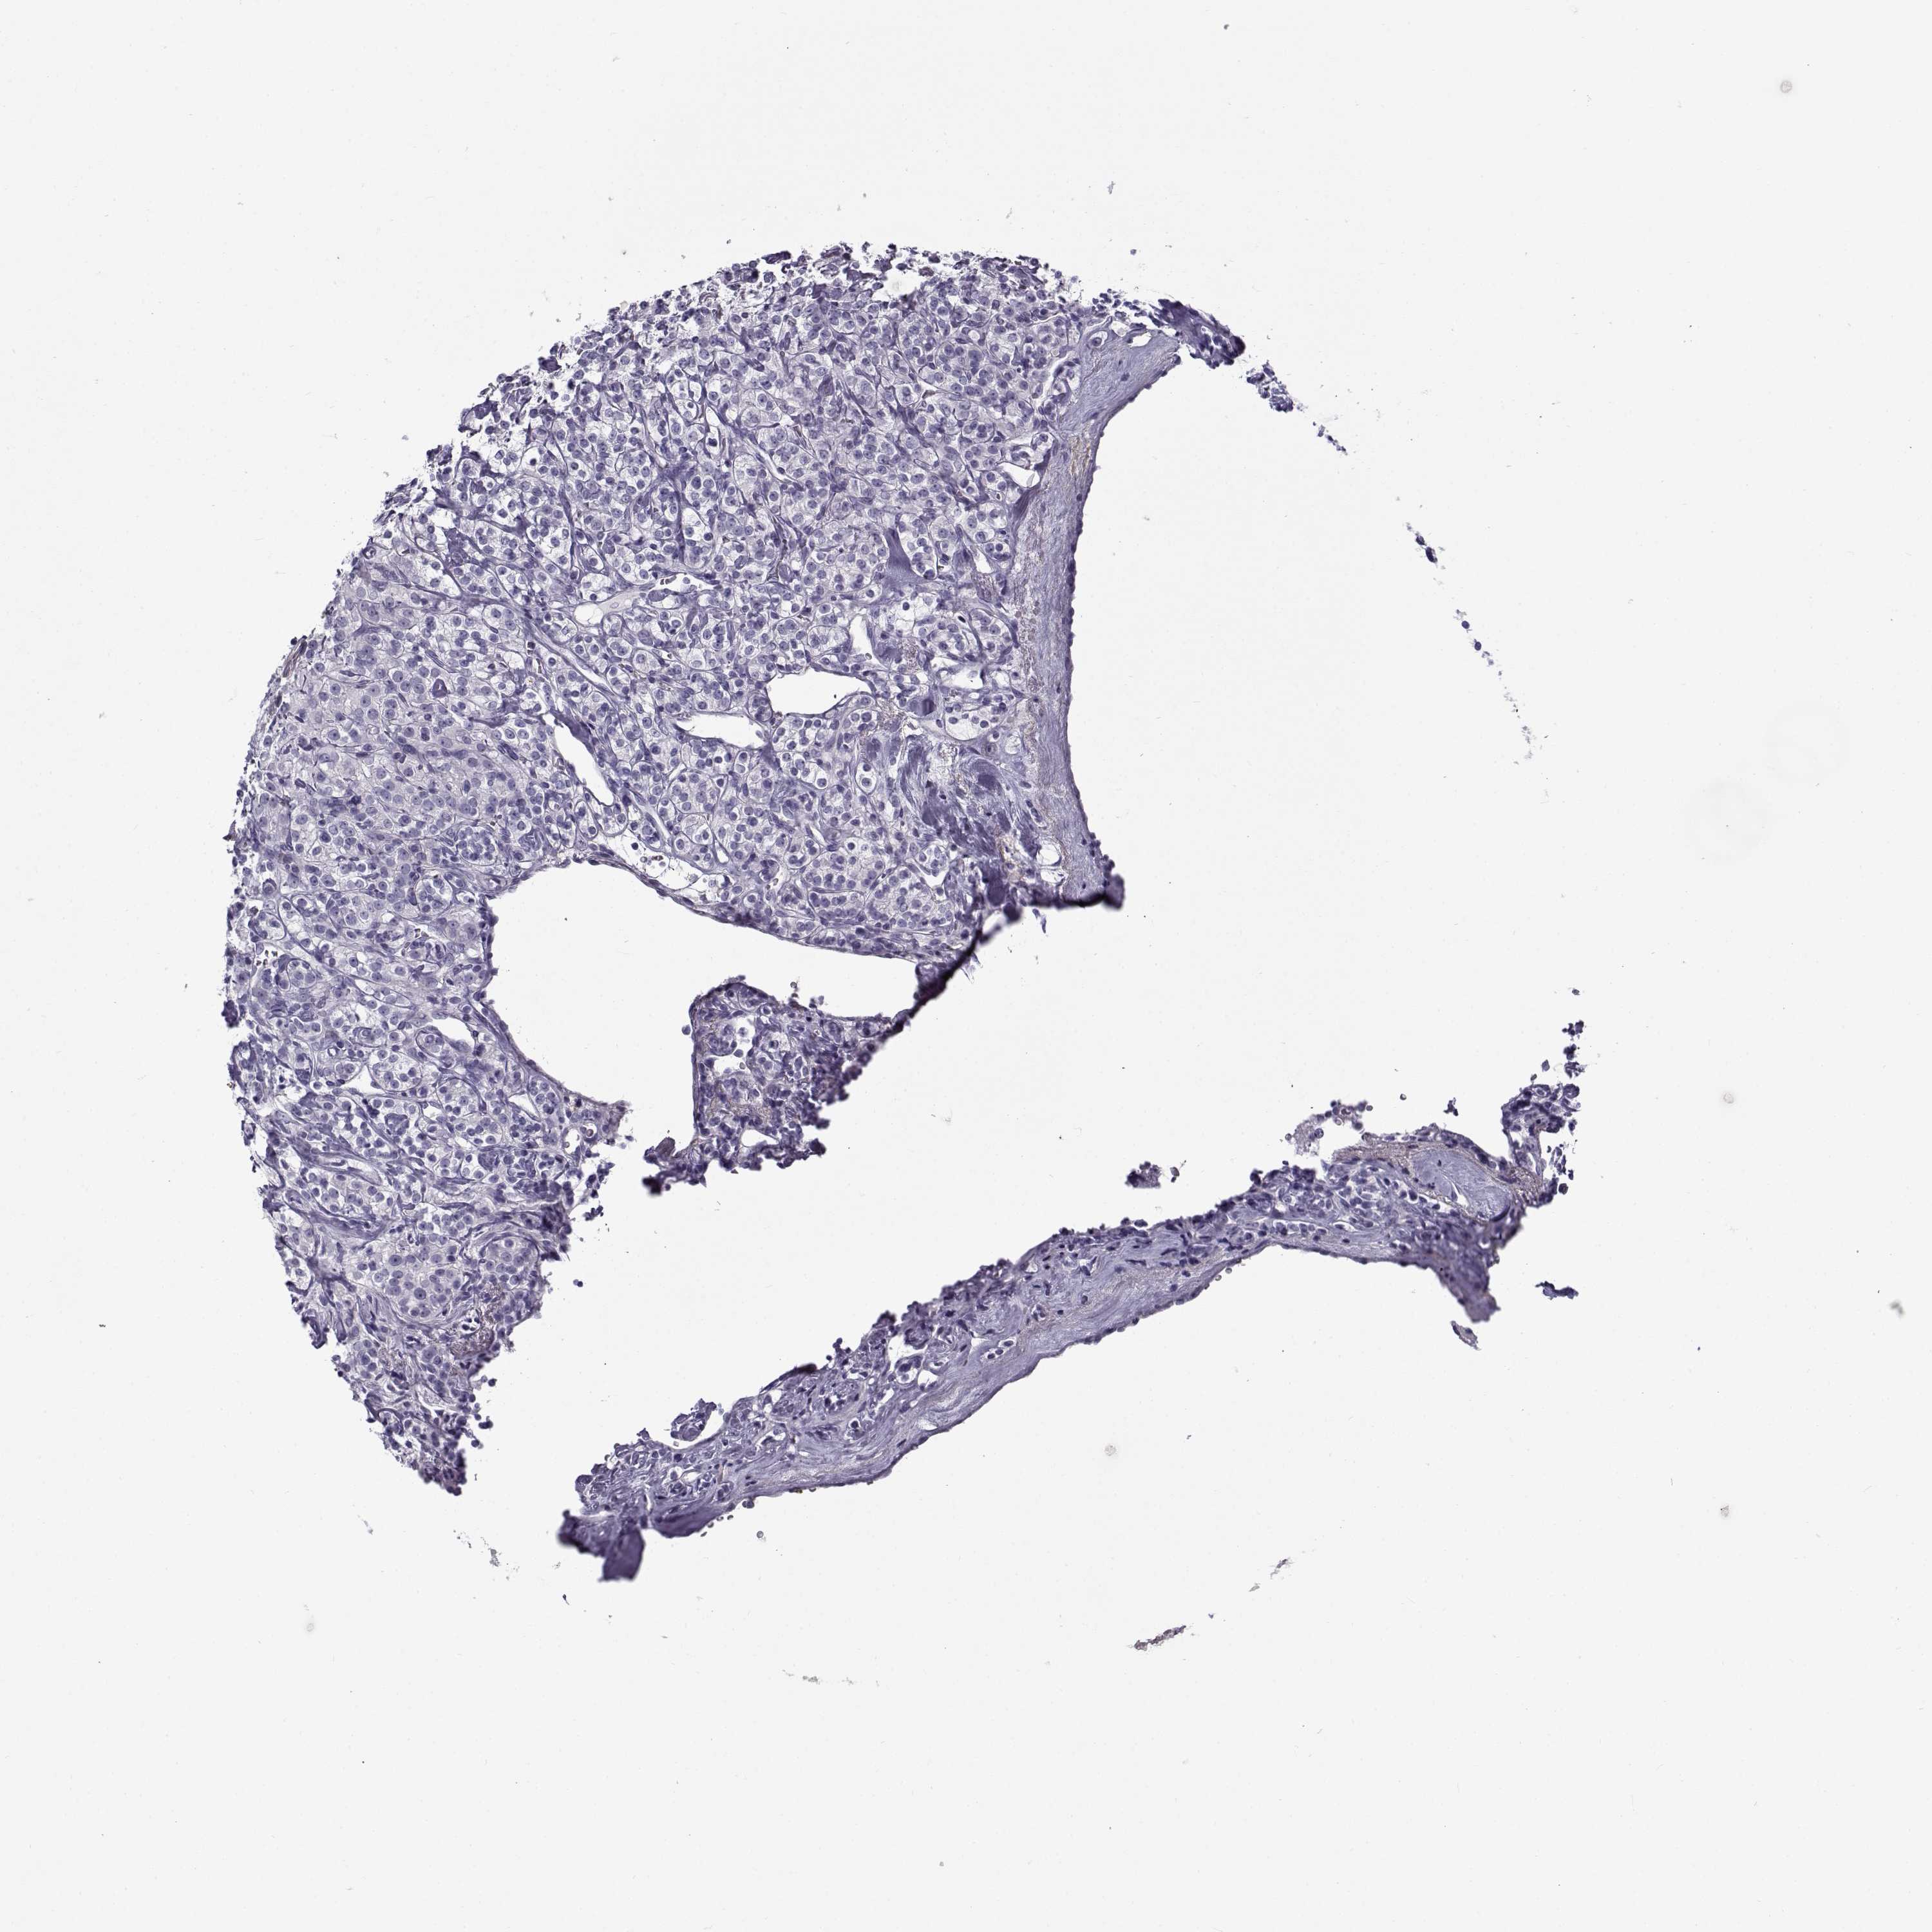

KIDNEY RENAL CLEAR CELL CARCINOMA (VALIDATION) - Interactive survival scatter ploti

The Survival Scatter plot shows the clinical status (i.e. dead or alive) for all individuals in the patient cohort, based on the same data that underlies the corresponding Kaplan-Meier plots. Patients that are alive at last time for follow-up are shown in blue and patients who have died during the study are shown in red.

The x-axis shows the expression levels (FPKM) of the investigated gene in the tumor tissue at the time of diagnosis. The y-axis shows the follow-up time after diagnosis (years). Both axes are complimented with kernel density curves demonstrating the data density over the axes. The top density plot shows the expression levels (FPKM) distribution among dead (red) and alive patients (blue). The right density plot shows the data density of the survived years of dead patients with high and low expression levels respectively, stratified using the cutoff indicated by the vertical dashed line through the Survival Scatter plot. This cutoff is automatically defined based on the FPKM cutoff that minimizes the p-score. The cutoff can be changed by dragging the vertical line or by entering a cutoff value in the square labeled "Current cut-off".

Under the Survival Scatter plot the p-score landscape (black curve; left axis) is shown together with dead median separation (red curve; right axis). Dead median separation is the difference in median mRNA expression between patients who have died with high and low expression, respectively. It is calculated as follows: median FPKM expression of dead patients with high expression - median FPKM expression of dead patients with low expression. This is intended to aid the user in visually exploring custom cutoffs and the associated p-scores and dead median separation.

Individual patient data is displayed and can be filtered by clicking on one or more of the category buttons on the top of the page. Categories describing expression level and patient information include: high, low, alive, dead, female, male and tumor stages. The scale of the x-axis can be toggled between linear and log-scale by clicking on the "x log" button. Mouse-over function shows TCGA ID, patient information and mRNA expression (FPKM) for each patient.

& Survival analysisi

Kaplan-Meier plots summarize results from analysis of correlation between mRNA expression level and patient survival. Patients were divided based on level of expression into one of the two groups "low" (under cut off) or "high" (over cut off). X-axis shows time for survival (years) and y-axis shows the probability of survival, where 1.0 corresponds to 100 percent.

GTSF1L is not prognostic in Kidney Renal Clear Cell Carcinoma (validation)

TCGA RNA samplesi

RNA-seq data is reported as average FPKM (number Fragments Per Kilobase of exon per Million reads), generated by the The Cancer Genome Atlas (TCGA) .

Normal distribution across the dataset is visualized with box plots, shown as median and 25th and 75th percentiles. Points are displayed as outliers if they are above or below 1.5 times the interquartile range. FPKM values of the individual samples are presented next to the box plot.

Average pTPM 0.2

Number of samples 100